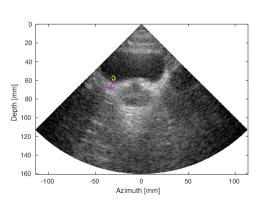

Results and discussion. Figure 3 and S- (in the supplementary material)

depict the SLT groundtruth, and the artifact-corrected and MLT images. Figure 3 demonstrates a number of anatomical structures in abdominal area, as depicted by the arrows. The CNN processing has restored the CR loss caused by the MLT cross-talk artifact for the MLT, and improved the CR by a dB for the MLT, as measured for aorta (yellow contour) and a background region (magenta contour). S demonstrates structures in a tissue mimicking phantom, such as anechoic cyst (the black circle marked by a yellow rectangle) and number of a point reflectors. Finally, S demonstrates a bladder (large dark cavity) and a prostate, located beneath it, scanned in a transversal plane. The output of our CNN was compared to the MLT image with Tukey () window apodization on receive, a common method to the attenuation of the receive cross-talk artifact.

| (d) MLT, (Tukey, =0.5) | (e) MLT, CNN | ||

| CNR=2.44, CR= -23.01dB | CNR= 2.53, CR=-32.81dB |